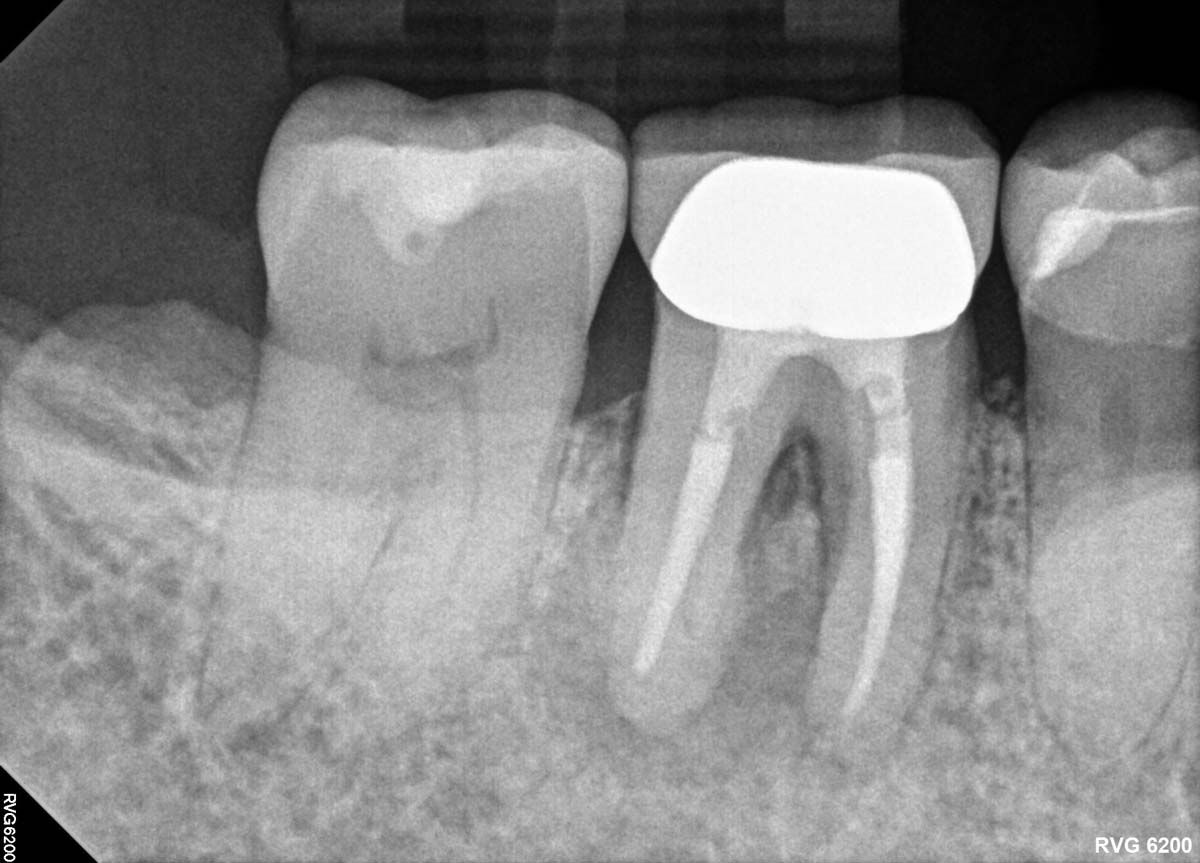

Infection was identified on pariapical x-rays.

A look at patient's periapical x-rays.